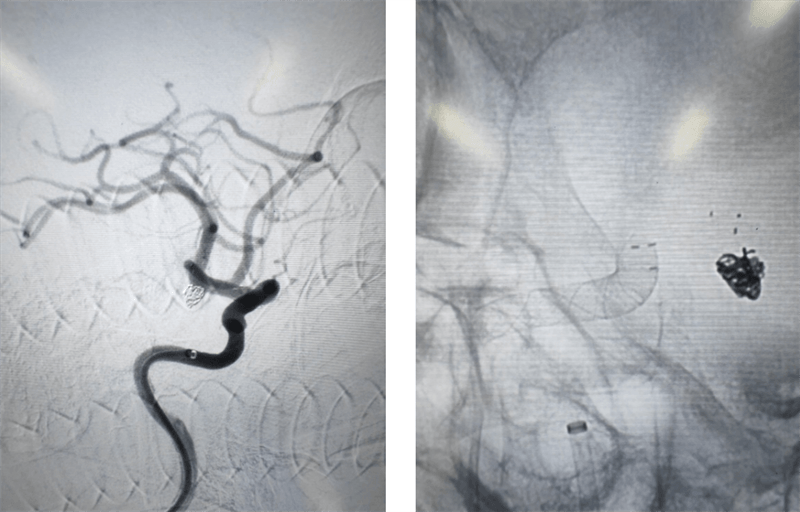

(術(shù)前3D造影)

術(shù)中,介入團(tuán)隊(duì)對患者右側(cè)頸內(nèi)動(dòng)脈末端兩枚動(dòng)脈瘤采用密網(wǎng)支架覆蓋,左側(cè)脈內(nèi)動(dòng)脈末端動(dòng)脈瘤采用彈簧圈填塞。在手術(shù)過程中,對患者左側(cè)頸內(nèi)動(dòng)脈使用6F長鞘,6F中間導(dǎo)管建立通路 ,分別使用X17 與headway-17微導(dǎo)管輸送Atlas輔助支架和數(shù)枚彈簧圈完成填塞。右側(cè)頸內(nèi)動(dòng)脈使用導(dǎo)引導(dǎo)管 GC-088-09 顱內(nèi)支撐導(dǎo)管同軸,在導(dǎo)絲引導(dǎo)下,將遠(yuǎn)端通路導(dǎo)管DA6115ST至右側(cè)頸內(nèi)動(dòng)脈海綿竇段。選擇合適工作角度,沿神經(jīng)血管導(dǎo)絲TNGW-14-200-S將TJMC18 Plus微導(dǎo)管送至大腦中動(dòng)脈,沿TJMC18 Plus送入NUVA 4.5*25mm血流導(dǎo)向密網(wǎng)支架, 支架順利打開。支架釋放后造影可見支架顯影清晰,形態(tài)良好,無貼壁不良。支架釋放后觀察10分鐘,無異常。經(jīng)過幾個(gè)小時(shí)的奮戰(zhàn),手術(shù)終于順利結(jié)束,患者重獲健康。

術(shù)后影像